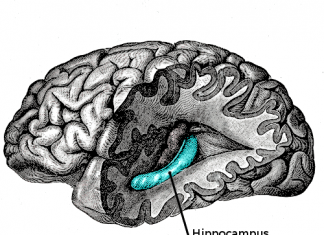

醫療 AI 獨角獸 HeartFlow 的心臟血流分析軟體獲 FDA 批准

冠心病經常漏診與誤診,之所以讓醫生難以診斷,是因為目前的檢測手段仍採用侵入性和高成本的血管造影。